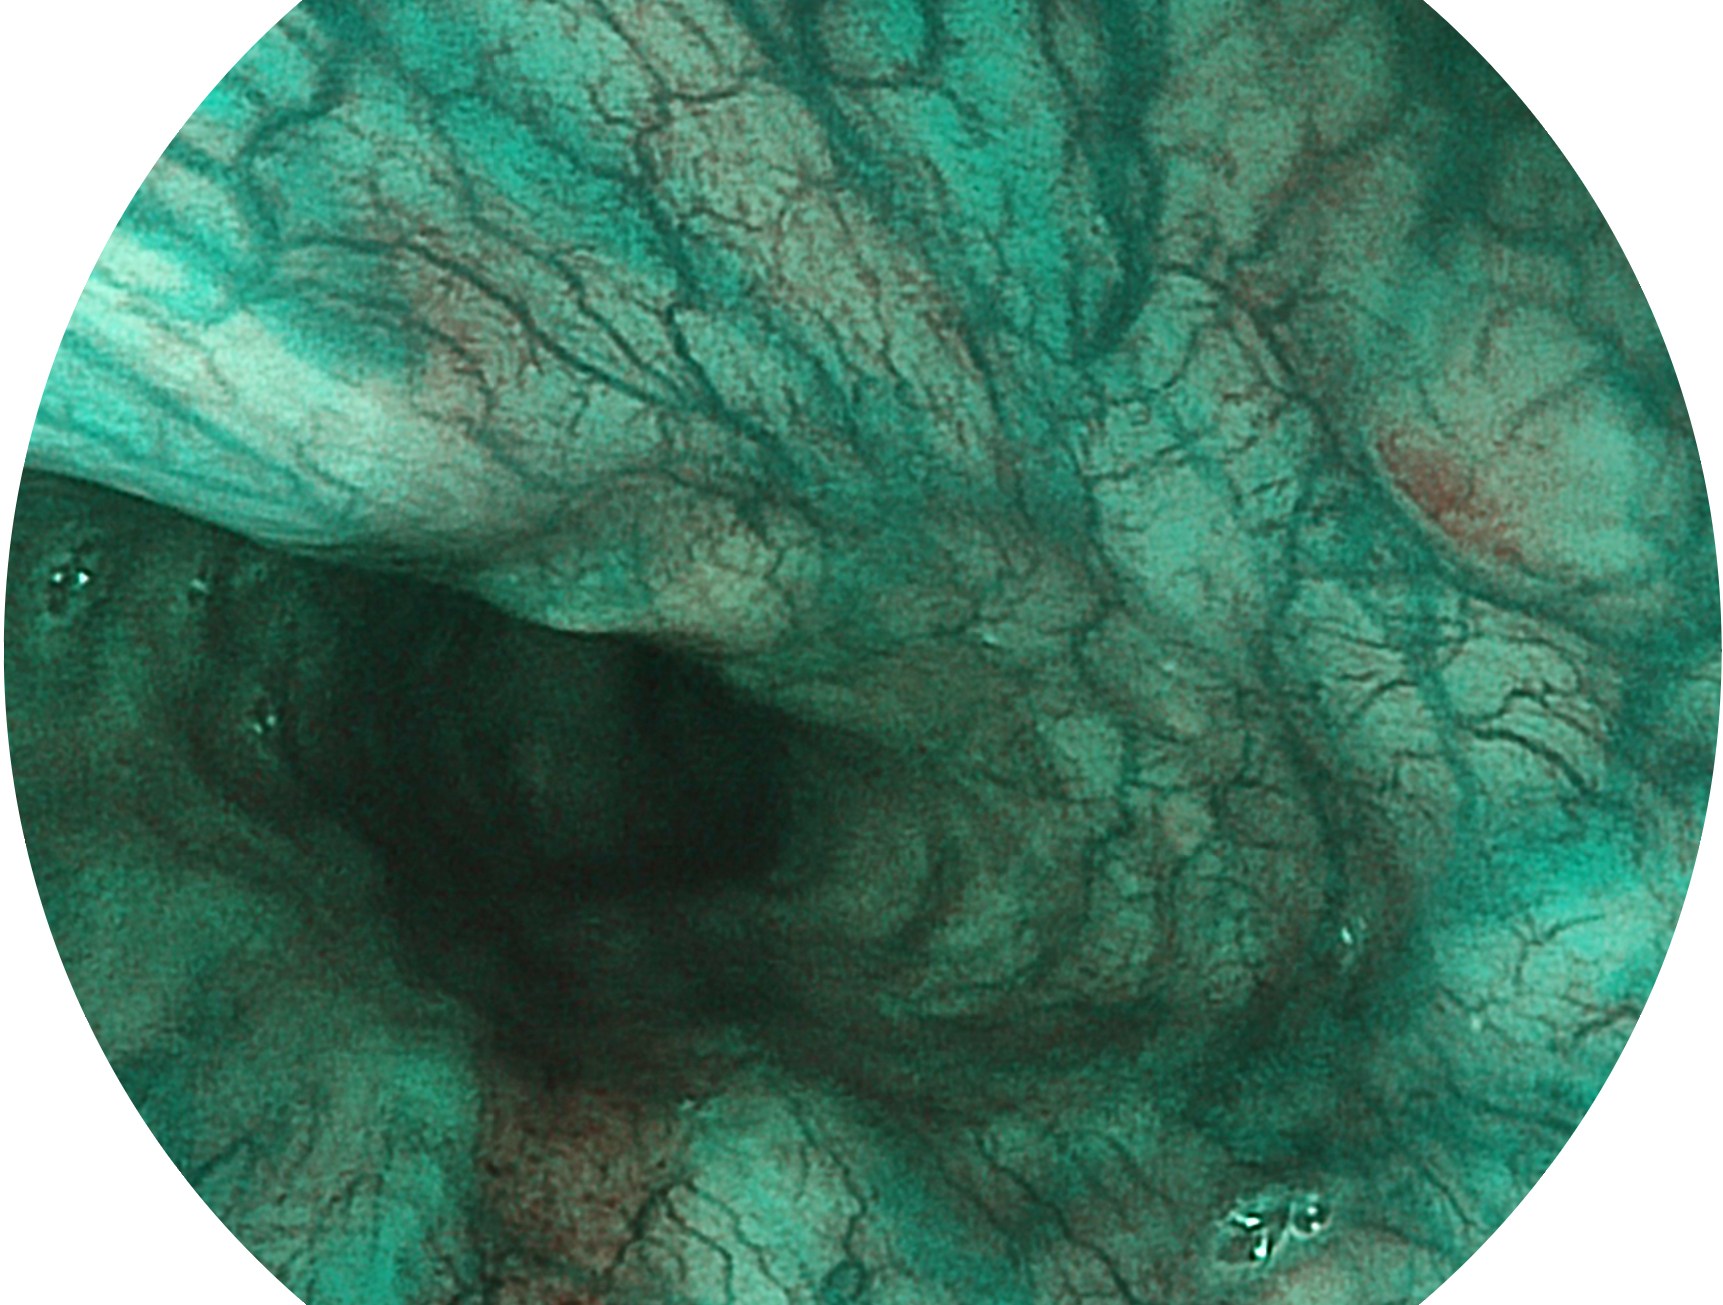

狗万官方网站新开发的内镜染色技术,主要是基于多波长LED 光源的开发,VLS-55Q 四波长LED 光源是由四个不同颜色的LED光按照相应照明模式所规定的特定发光比例进行合束后形成,合束后形成的照明光的光谱由红光、绿光、蓝光及蓝紫光这四个不同的波段范围构成。具有更高光谱自由度,通过光谱比例的控制,实现了聚谱成像技术,英文全称为“Spectral Focused Imaging, SFI”,缩写为“SFI”和光电复合染色成像技术,英文全称为“Versatile Intelligent Staining Technology, VIST”,缩写为“VIST”。